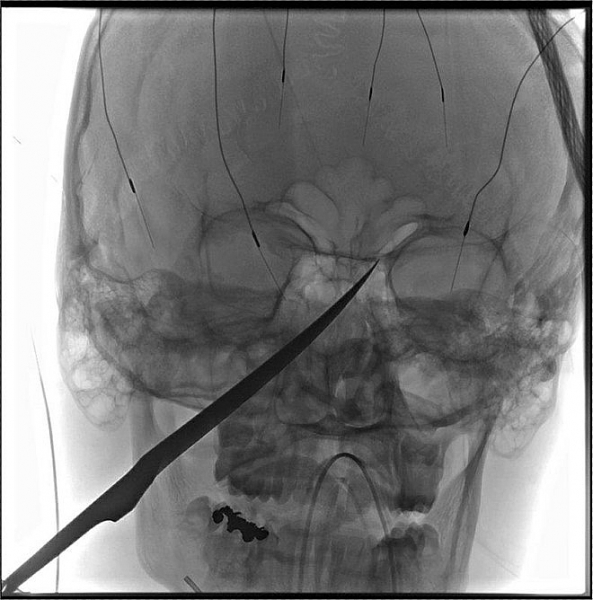

Cậu bé Mỹ 15 tuổi bị dao đâm xuyên hộp sọ sống sót kỳ diệu

Lưỡi dao đã đâm xuyên vào hộp sọ và suýt chạm tới não của Gregg. Mũi dao khi đó gần chạm tới động mạch cảnh, nơi cung cấp máu cho não, theo AP.

Bác sĩ Koji Ebersole, người phụ trách điều trị cho Gregg, nói về sự may mắn của bệnh nhân: "Tôi không thể tin rằng cậu bé vẫn còn sống. Nếu chỉ đâm sâu thêm một chút thì cậu bé không thể qua khỏi".

Nhóm bác sĩ cùng nhau lập ra kế hoạch phẫu thuật phức tạp để lấy con dao khỏi mặt Gregg vào sáng hôm sau. Họ thậm chí phải chuẩn bị trước trong trường hợp Gregg chảy máu não. Cuối cùng, ca phẫu thuật đã diễn ra suôn sẻ và không gặp trở ngại nào. Động mạch vẫn còn nguyên vẹn.

| Cậu bé may mắn được các bác sĩ phẫu thuật thành công vào sáng 14/6. Ảnh: AP. |